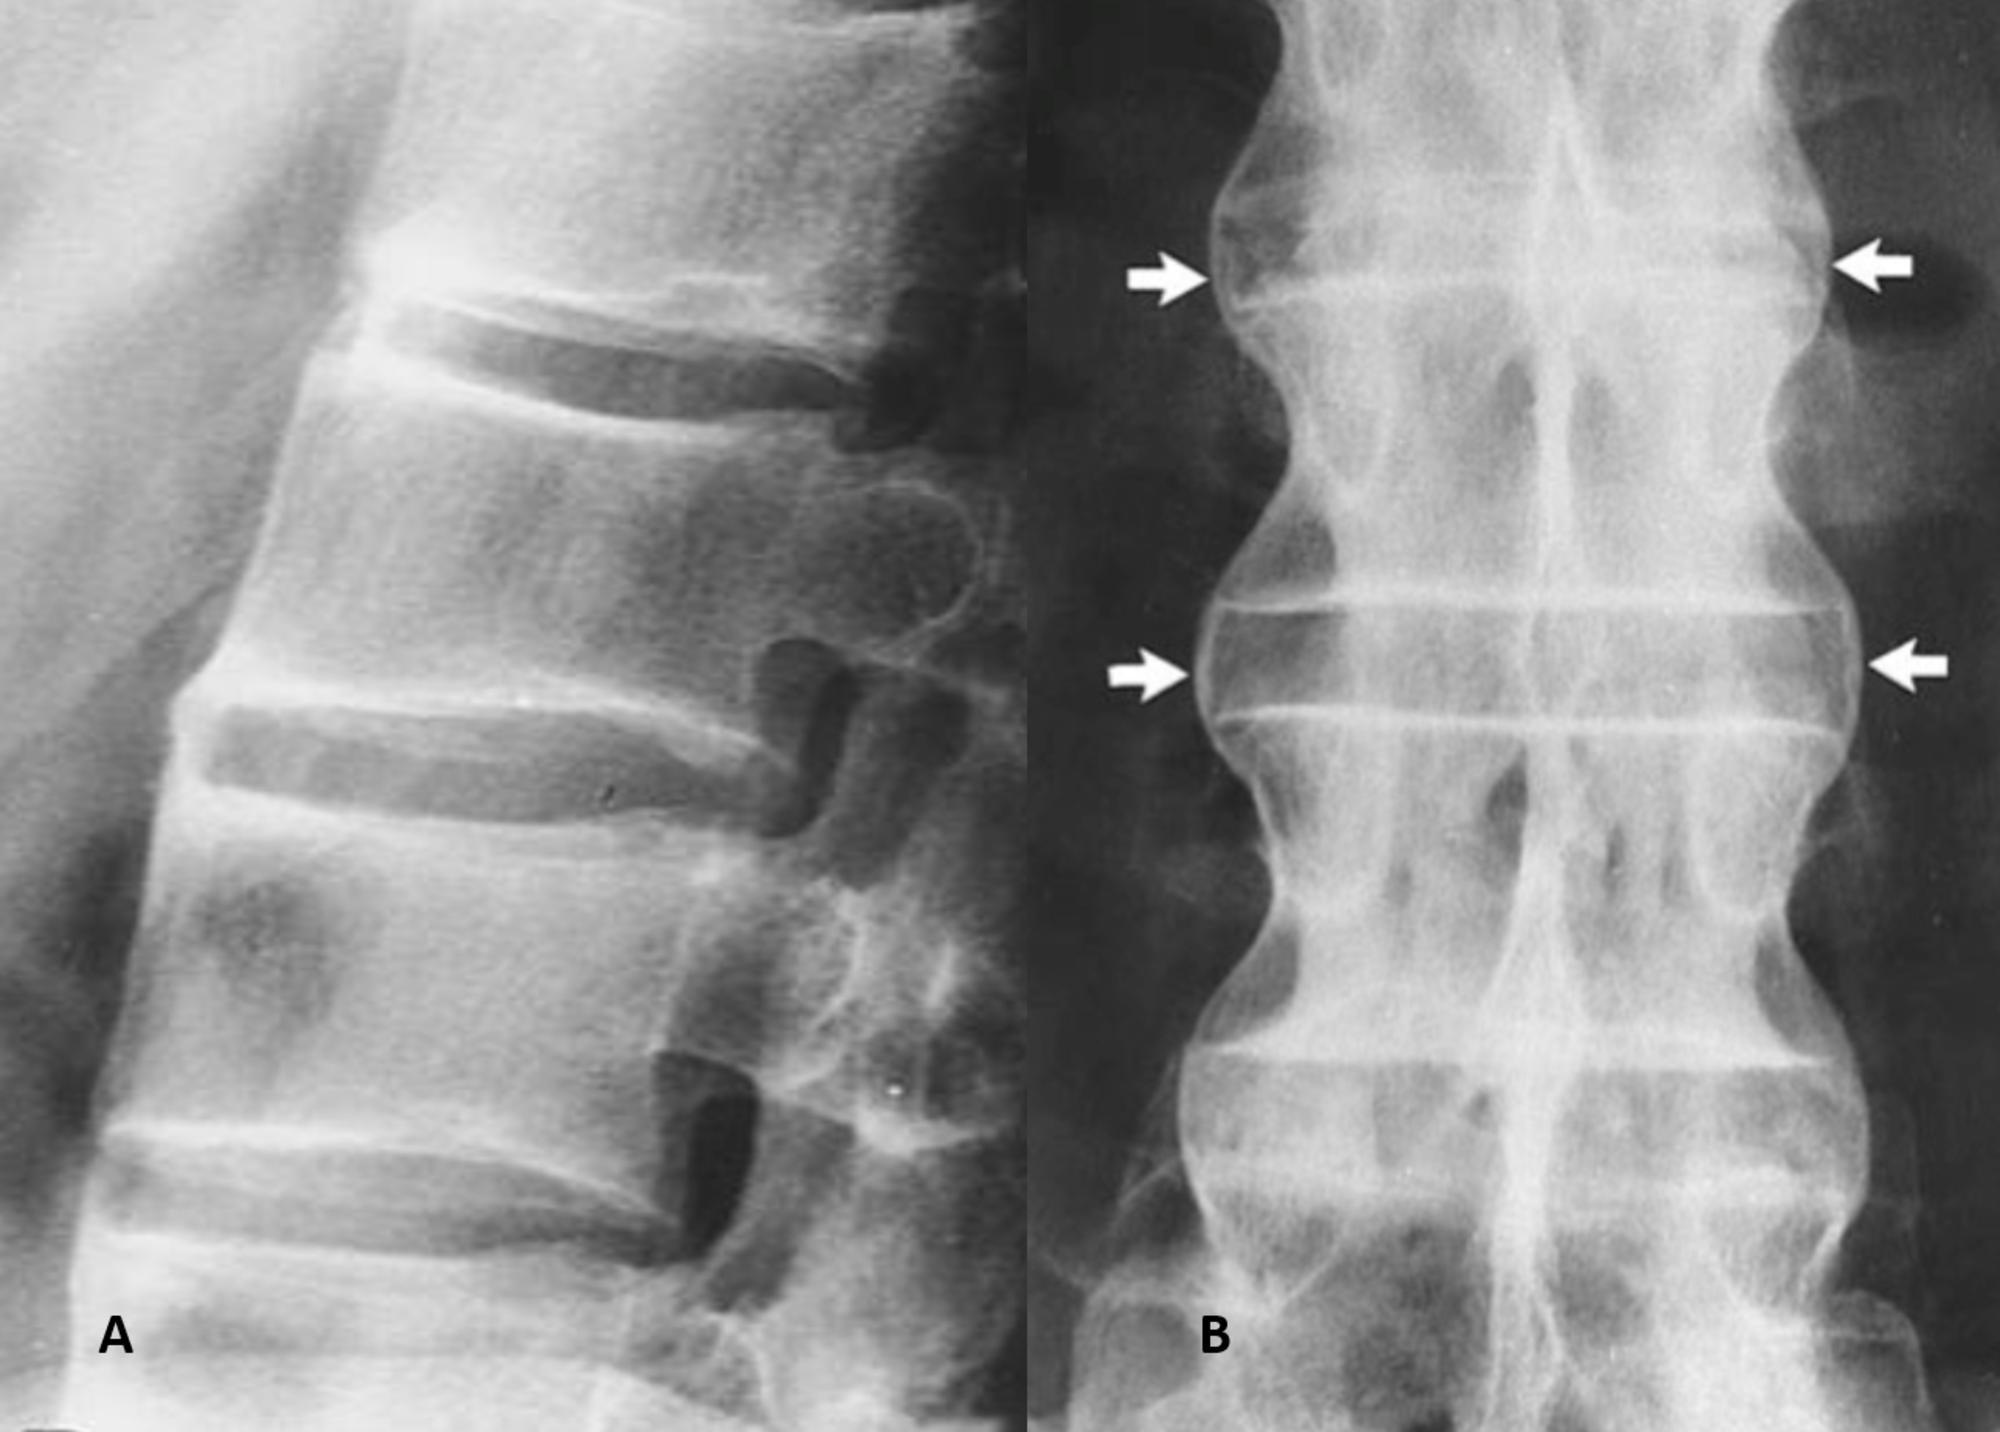

Saraf kejepit atau dalam istilah medis dikenal sebagai “nerve compression” adalah kondisi di mana saraf mengalami tekanan berlebihan sehingga aliran sinyal yang seharusnya lancar menjadi terganggu.

Gangguan ini dapat muncul akibat beberapa faktor, seperti cedera fisik, herniasi diskus, penebalan jaringan ikat, atau proses degeneratif pada tulang dan cakram tulang belakang.

Misalnya, pada kasus herniasi diskus tulang belakang, lapisan luar cakram yang merenggang atau pecah dapat menekan saraf yang berada di sekitarnya. Tekanan ini menyebabkan inflamasi serta gangguan fungsi saraf, menghasilkan sensasi nyeri, kebas, atau bahkan kelemahan otot.

Dokter bedah saraf dapat melakukan evaluasi menyeluruh menggunakan berbagai metode diagnostik, mulai dari pemeriksaan fisik hingga penggunaan teknologi pencitraan seperti MRI (Magnetic Resonance Imaging) dan CT scan untuk mengetahui sumber sekaligus tingkat keparahan penekanan saraf.